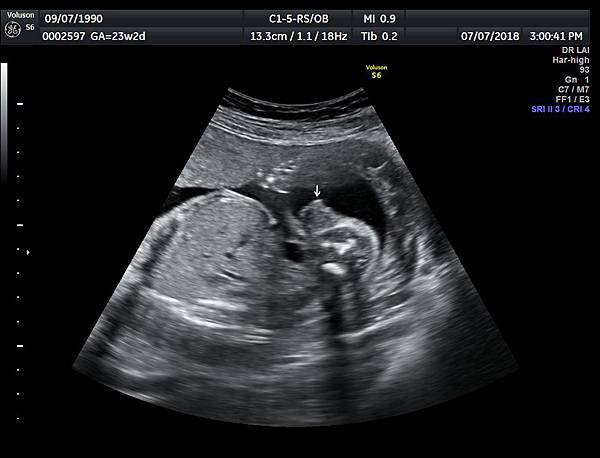

今天下午一位28歲第一胎的孕婦來診所做超音波檢查,之前他們一直認為懷的是女兒(檢查前資料顯示胎兒是女生);今天我的診斷胎兒是男生,但是懷疑有尿道下裂的問題(附圖 1~4),我的建議是抽羊水做染色體基因檢查,除了確定性別之外,也可以排除是否合併基因異常。

診斷尿道下裂常用的鬱金香sign(tulip sign)(附圖 10.11.),它的特徵就是龜頭陷入陰囊中間,胎兒如果是男生,一定要看到龜頭離開陰囊,這樣就沒有問題,每次遇到尿道下裂的個案時,我都會有一個感觸,男生如果能站著尿尿都要很感恩。